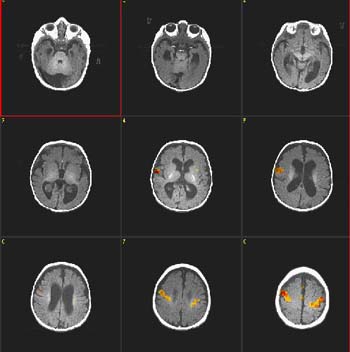

Niño de 4 años de edad con autismo

ACTIVADO: Presentación de luces intermitentes a 8 Hz, con gafas especiales colocadas

DESACTIVADO: Nada. Paciente sedado con nembutal |

| Prueba T |

0,000002 |

4,0 |

| Activación |

Cortes coronales. Las áreas coloreadas en la figura se obtuvieron restando ACTIVADO a DESACTIVADO. Por consiguiente, el resultado muestra "desactivación", lo que representa la hiperextracción de oxígeno en las áreas visuales primarias (V1). Este hallazgo aparece constantemente en niños pequeños, ya sea despiertos o bajo sedación. |